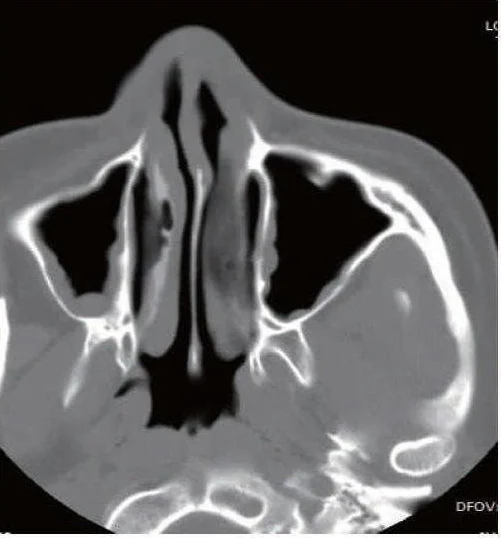

影像学检查是确诊慢性鼻窦炎的重要手段。CT扫描是目前最常用的影像学检查方法,通过CT可以清晰地显示鼻窦的结构,确定炎症的范围和程度,帮助医生制定治疗计划。